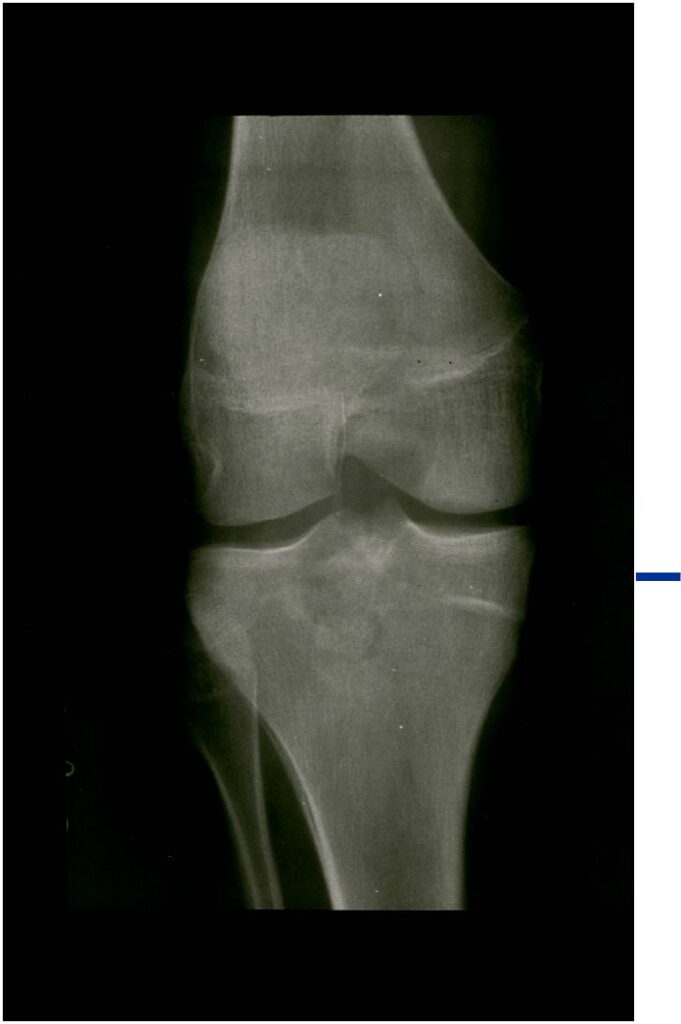

General Information Enchondroma is a benign indolent intramedullary hyaline cartilage neoplasm Accounts for 10% of all benign osseous tumors Limited growth, most lesions are less than 5 cm in maximal dimension Bones grow from a cartilaginous growth plate that...